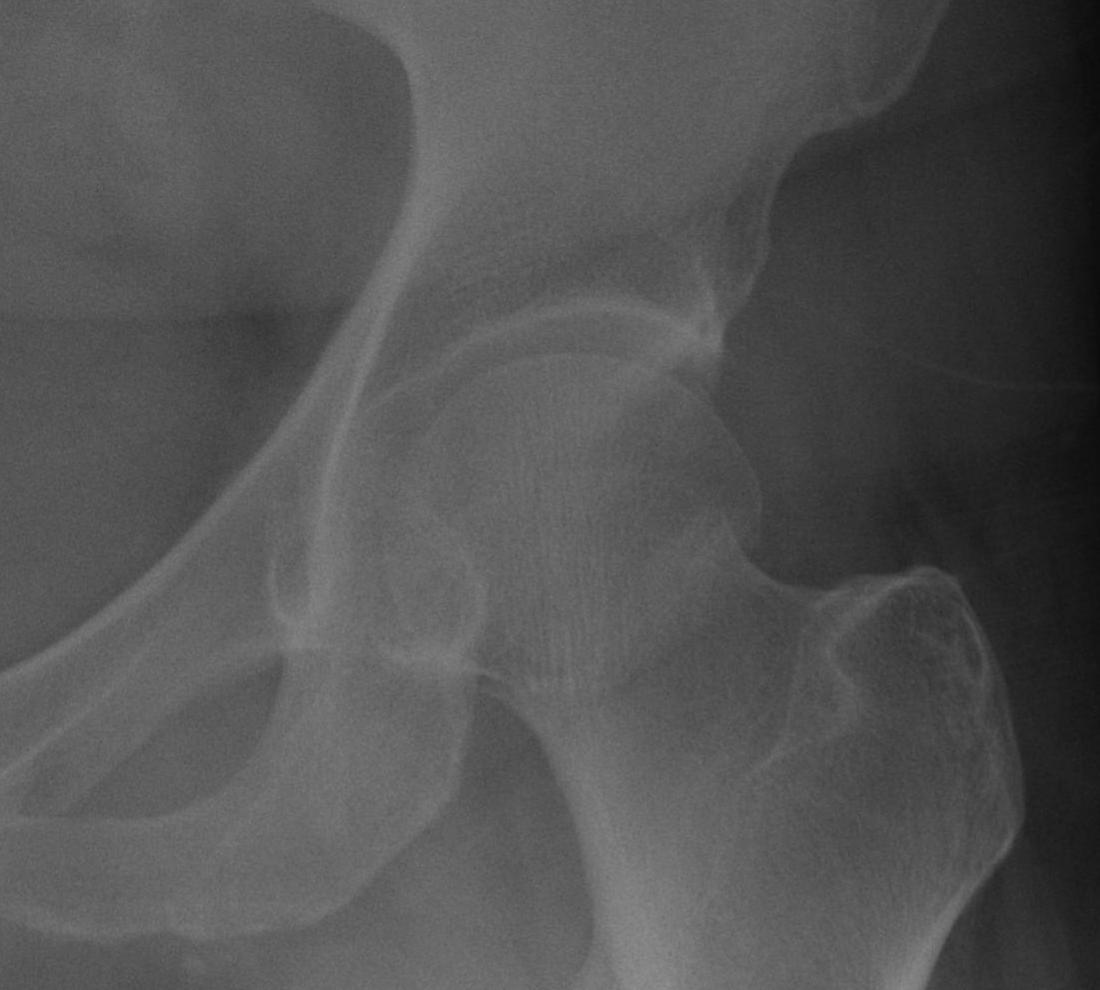

Garden's Classification

| Garden | Description | Displacement |

| I |

Incomplete Valgus impacted Lateral cortex fractured Medial cortex intact |

Undisplaced |

| II | Complete | Undisplaced |

| III |

Complete fracture Partial displacement Trabeculae don't line up with acetabulum |

Displaced |

| IV |

Complete fracture Complete displacement Trabeculae line up with acetabulum |

Type I: Incomplete, valgus impacted fracture

Type II: Complete fracture, undisplaced

Type III: Complete fracture, partial displaced, trabeculae don't line up with acetabulum

Type IV: Complete fracture, completely displaced, trabeculae line up with acetabulum